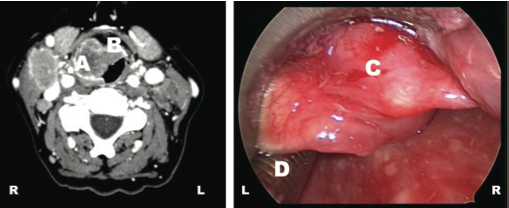

- Un CT de la región mostró una masa de 32X 26 mm que incluia el repliegue ariepiglótico derecho (A), y la base de la epiglotis (B). Tras realizar un intubación con paciente despierto mediante fibroscopio, se realizó una laringoscopia que evidencia la importante masa tumoral (C) que impide la visión de la glotis y de la porción distal del tubo endotraqueal (D).

CT Cervical: A. Repliegue ariepiglótico derecho, B. Epiglotis, C. Tumor de células de Merkel, D. Tubo endotraqueal